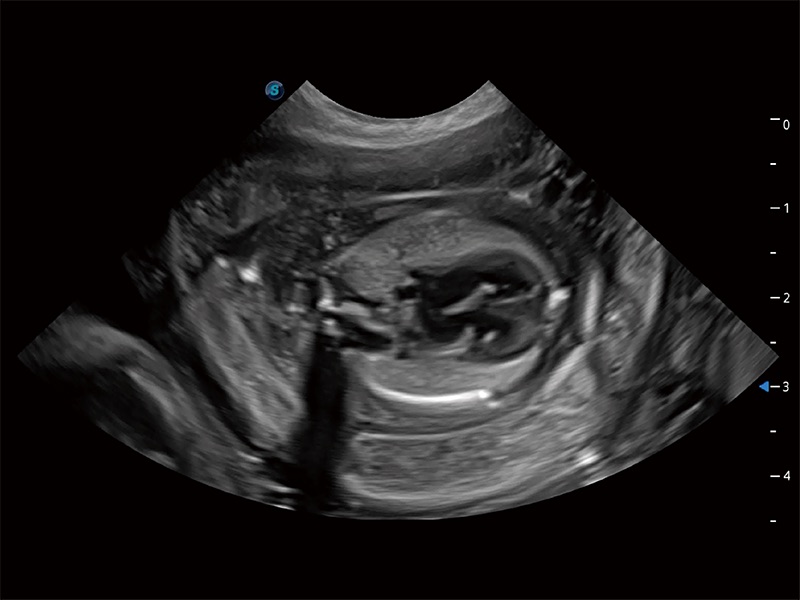

动物是人类最亲密的朋友和最值得信赖的伙伴。16877太阳集团也一直致力于探索动物专用的超声影像解决方案。全新推出的ProPet系列,是16877太阳集团在动物超声影像智能化、专业化、精准化的一次跨越式革新。动物不能用言语来表述自己的不适,通过超声影像,ProPet系列搭建了动物医生与不同物种沟通的“桥梁”,为动物医生注入了“治愈之力”。 ProPet 80 是16877太阳集团匠心打造的一款高端动物专用彩超,采用性能卓越的全新硬件架构,极大提升超声系统的运行效率和数据处理能力,帮助动物医生从容应对日益增多的挑战性病例和日益多样化的临床需求。

高性能和先进的临床应用工具可以为动物医生提供临床信心。ProPet 80 搭载了先进的腹部和浅表应用工具,帮助医生在日常临床实践中发挥前所未有的作用。